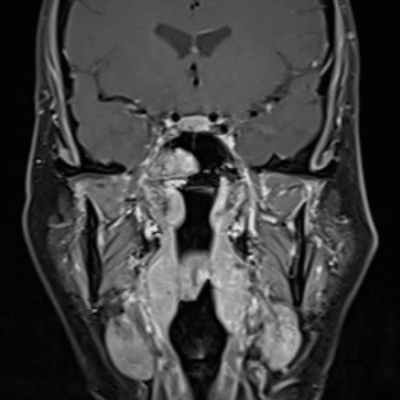

Annotated Images & Illustrations

Multiple enhancing mass involving the right skull base (red arrow), right nasolacrimal duct (yellow arrow), and left nasal cavity (blue arrows).